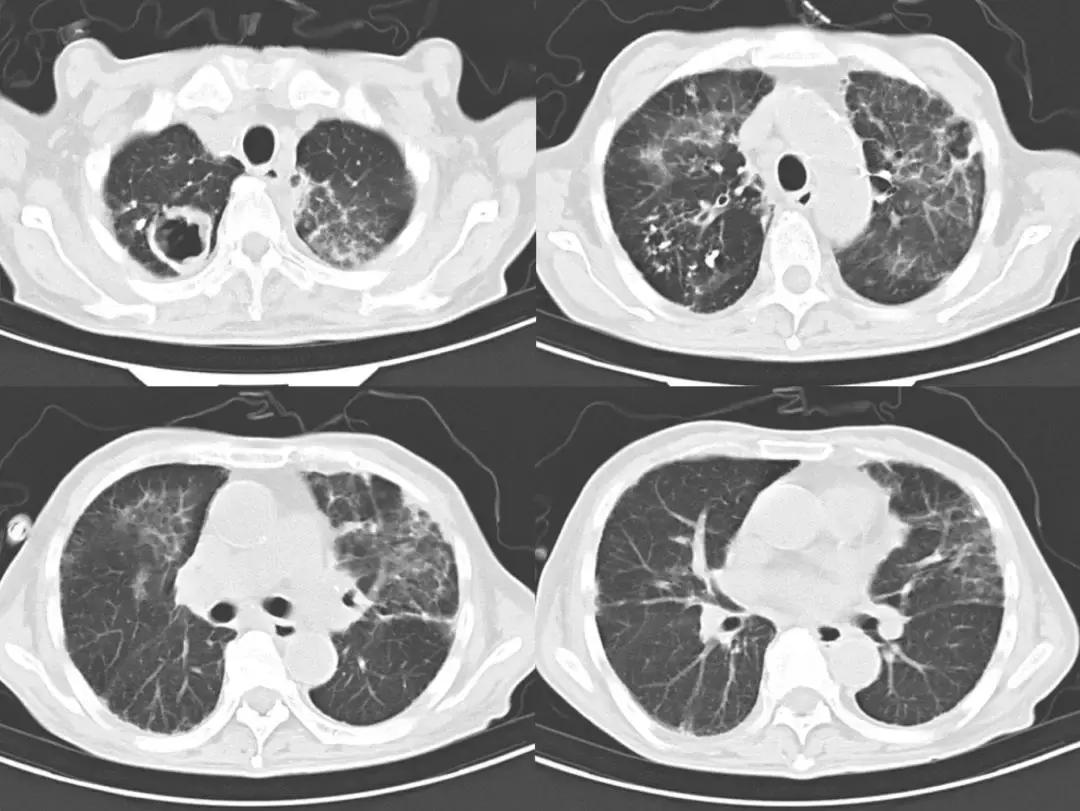

此后患者仍有发热,调整抗生素为比阿培南+利奈咗胺后加强抗感染治疗,体温仍波动在39℃。复查胸部CT(2018-8-20)示:右肺上叶厚壁空洞,两肺上叶及左肺下叶炎性渗出增多,左下少量胸腔积液(图2)。

图2

为进一步明确诊断,予以予以经皮胸腔穿刺抽液术,可见抽出黑色胸腔积液(图3)。胸腔积液mNGS结果回报:检出聚多曲霉 66个序列数。给予伏立康唑抗真菌治疗,患者咳嗽、咳痰明显好转,体温恢复正常。复查胸部CT(2018-8-25):肺部病灶较前明显好转(图4)。NGS结果回报后,通知检验科针对曲菌更改培养条件、延长培养时间,20多天后最终培养结果回报:聚多曲霉(图5)。患者出院后持续伊曲康唑抗真菌、正规抗结核治疗,未再出现发热,关节疼痛也明显好转,停用非甾体类止痛药和激素,随访中。

图4